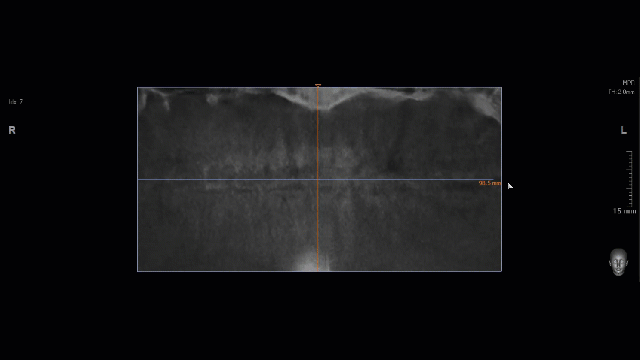

В 16 лет я увидел панорамный снимок на фото выше и, уже успев натерпеться стоматологии и врачей, я загрустил (я только что сильно болел фронтитом и гайморитом в 15 лет, в 7 классе только перестав носить пластинку, я побежал, споткнулся и выбил передние зубы о бетонную плиту). Я спросил врача в Красноярске, который анализировал снимок, мол что же делать с лишними зубами (а тогда они еще не особо мешали и только слегка прощупывались)? Я получил довольно точный ответ в духе - нужно надрезать десну, отворачивать ее, сверлить кость и удалять зубы. Это меня впечатлило настолько, что я отложил решение этого вопроса аж до 29 лет. Да и не до этого как-то было.

Картина на начало процесса и пара слов про зубы мудрости

Картинка не архисложная, но и не простая: